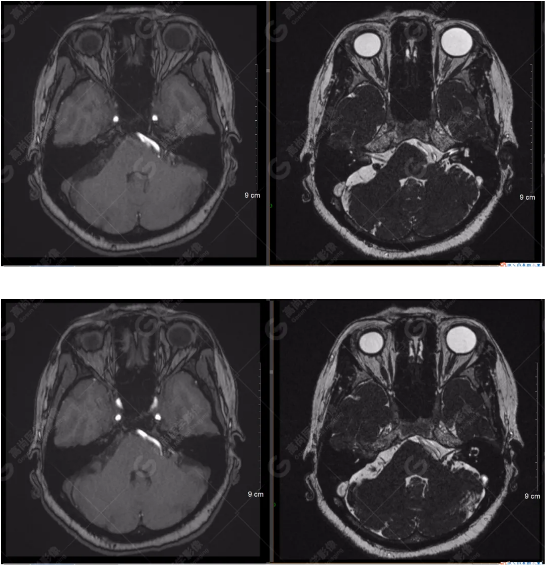

檢查圖像

顱腦MRA及ciss序列示腦基底動(dòng)脈環(huán)完整,雙側(cè)頸內(nèi)動(dòng)脈末段、大腦前動(dòng)脈、大腦中動(dòng)脈、大腦后動(dòng)脈及其主要分支顯影良好,管徑及走行正常,無明顯局灶性增粗或變細(xì)。雙側(cè)椎動(dòng)脈末段沿延髓左側(cè)向上走行,左側(cè)面聽神經(jīng)輕度受壓移位,左側(cè)面聽神經(jīng)周圍見細(xì)小血管包繞。右側(cè)面聽神經(jīng)及雙側(cè)三叉神經(jīng)周圍未見異常血管影。

1.雙側(cè)椎動(dòng)脈末段沿延髓左側(cè)向上走行,左側(cè)面聽神經(jīng)輕度受壓移位,左側(cè)面聽神經(jīng)周圍見細(xì)小血管包繞,可符合面聽神經(jīng)壓迫綜合征。